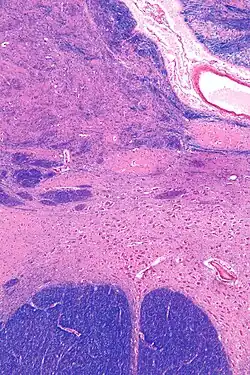

MRI showing a coronal plane of the head with marks showing the location of the substantia innominata, the region in which the nucleus basalis is found. | |